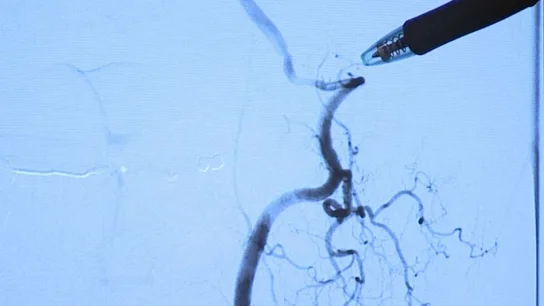

Halder tuvo que recibir atención médica inmediata, ya que se había roto una vértebra y había sufrido un derrame cerebral. El doctor Vance McCollom del Mercy Hospital ha declarado ante la televisión local de Oklahoma 'Koco' que estirar el cuello coloca las arterias vertebrales en una delicada posición que pueden provocar graves lesiones, aunque el riesgo "es pequeño", por lo general.